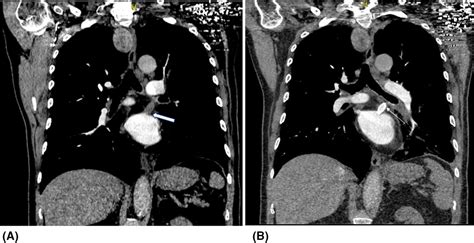

Computed Tomography (CT) Scan Provides detailed images of the pulmonary veins and surrounding structures, helping to identify the location and extent of stenosis.